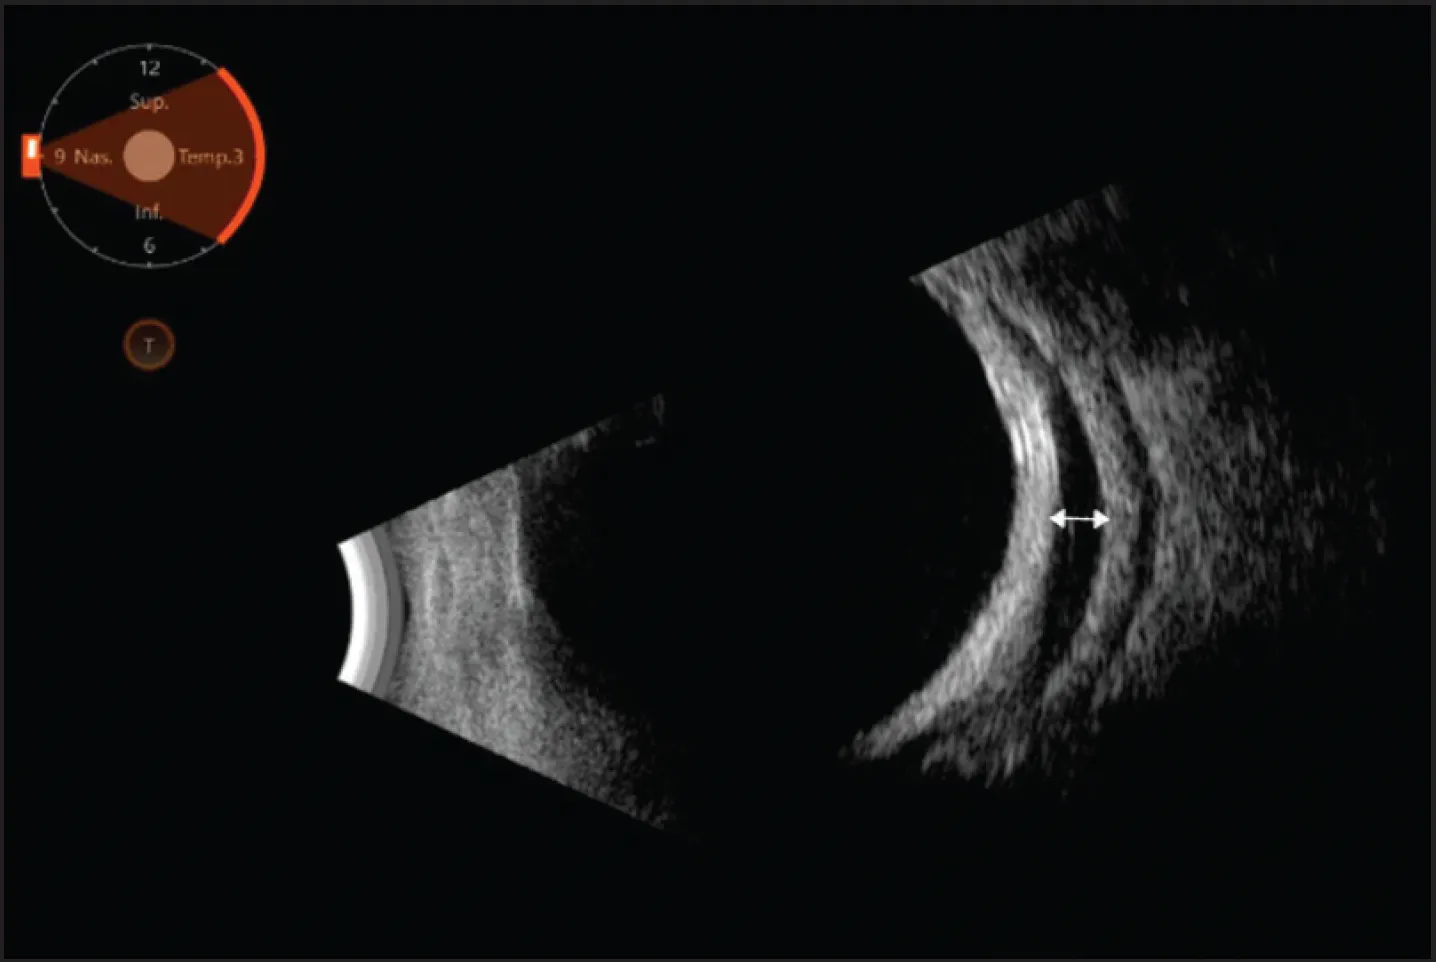

Visualization on indirect ophthalmoscopy is possible when choroidal detachments are large, encroaching on the macula or kissing. When the detachment is more anterior, however, diagnosis and classification can be achieved through B-scan ultrasound imaging. A well-circumscribed, smooth, and dome-shaped membrane will be visible rising in a convex shape into the vitreous cavity (Figure 2). Unlike retinal detachments, choroidal detachments are immobile and can extend past the ora serrata on B-scan ultrasound. The space beneath the membrane appears hypoechoic in serous choroidal detachments (Figure 2) and hyperechoic in hemorrhagic choroidal detachments—a distinction that can be crucial for management.1,2,6,7

Figure 2. Serous choroidal detachment is demonstrated with a shallow hyperechoic membrane overlying the hypoechoic transudative fluid (white arrow) on B-scan ultrasound.